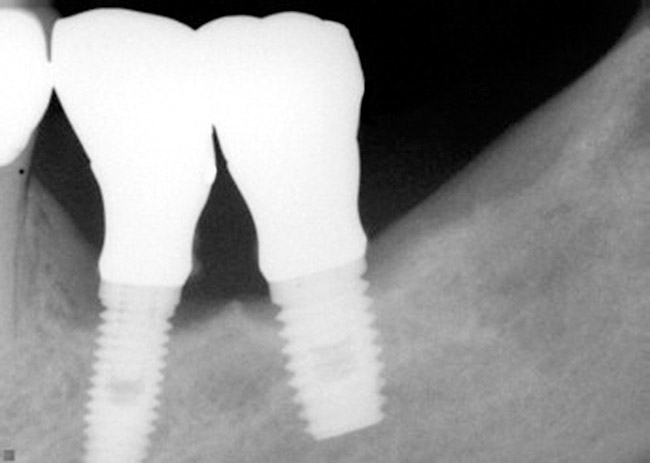

Radiographically, in peri-implantitis, vertical destruction of the crestal bone is present around the implant—which assumes the shape of a saucer—while the bottom part of the implant remains osseointegrated. In some instances, wedge-shaped defects develop along the implant (Figure 1). In addition, there is a peri-implant pocket and bleeding after gentle probing with a blunt instrument, and there may be suppuration from the pocket (Figure 2 and Figure 3). Tissues may or may not be swollen; however, hyperplasia is frequently seen if implants are located in an area with non-keratinized mucosa or if the suprastructure is an overdenture. Pain is not present.9 Both a mean loss of peri-implant bone height amounting to 1 mm to 1.5 mm in the first postsurgical year and vertical bone loss of less than 0.2 mm annually following the implant’s first year of service have been proposed as major criteria for success.18-20 It should be noted that peri-implant bone loss also occurs in cases of overload and faulty occlusion and may be be related to the type of implant used. The implants with the longest smooth surfaces demonstrated the highest amounts of bone resorption 12 months after abutment connection.21 Mobility of an implant suggests complete bone loss and, therefore, complete failure. To prevent this, peri-implant disease should be recognized earlier, to allow intervention before a substantial portion of the supporting bone is lost. However, mobility in early periods of osseointegration is not a very reliable clinical indicator of peri-implantitis. Therefore, electronic measuring devices should be used.

Figure 1